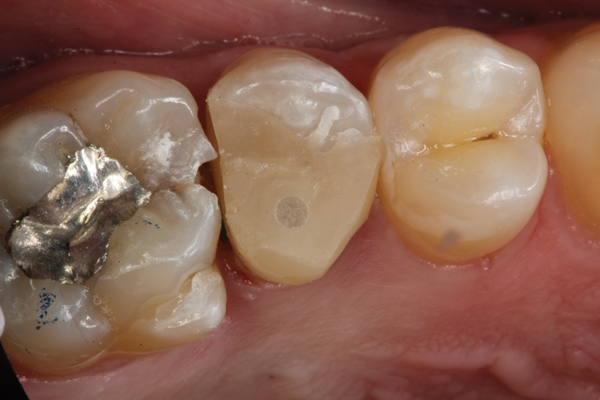

Higher viscosity bulk-fill composites can be used up to the occlusal surface, however. Two clinical cases using the bulk-fill composites Tetric EvoCeram Bulk Fill and SonicFill are presented in Figure 2 through Figure 6. Limitations when placing a high-viscosity bulk-fill composite include difficulty of condensing and esthetic restraints. Condensing a high-viscosity resin composite ensures adequate adaptation to the tooth preparation and sufficient interproximal contacts. Condensing 4 mm of composite is more difficult than condensing 2 mm. To ensure adequate interproximal contacts, a sectional or circumferential matrix with an inciso-gingival curvature can be used to obtain a tight area of contact gingival to the marginal ridge. A ring should be used to help separate the teeth and improve the tightness of the contact area.

(2.) Preparation of tooth No. 31.

Figure 2

(3.) Restoration of tooth No. 31.

Figure 3

(4.) Preparation of tooth No. 19 with 4-mm distal box.

Figure 4

(5.) Placement of composite into tooth No. 19.

Figure 5

(6.) Restoration of tooth No. 19.

Figure 6